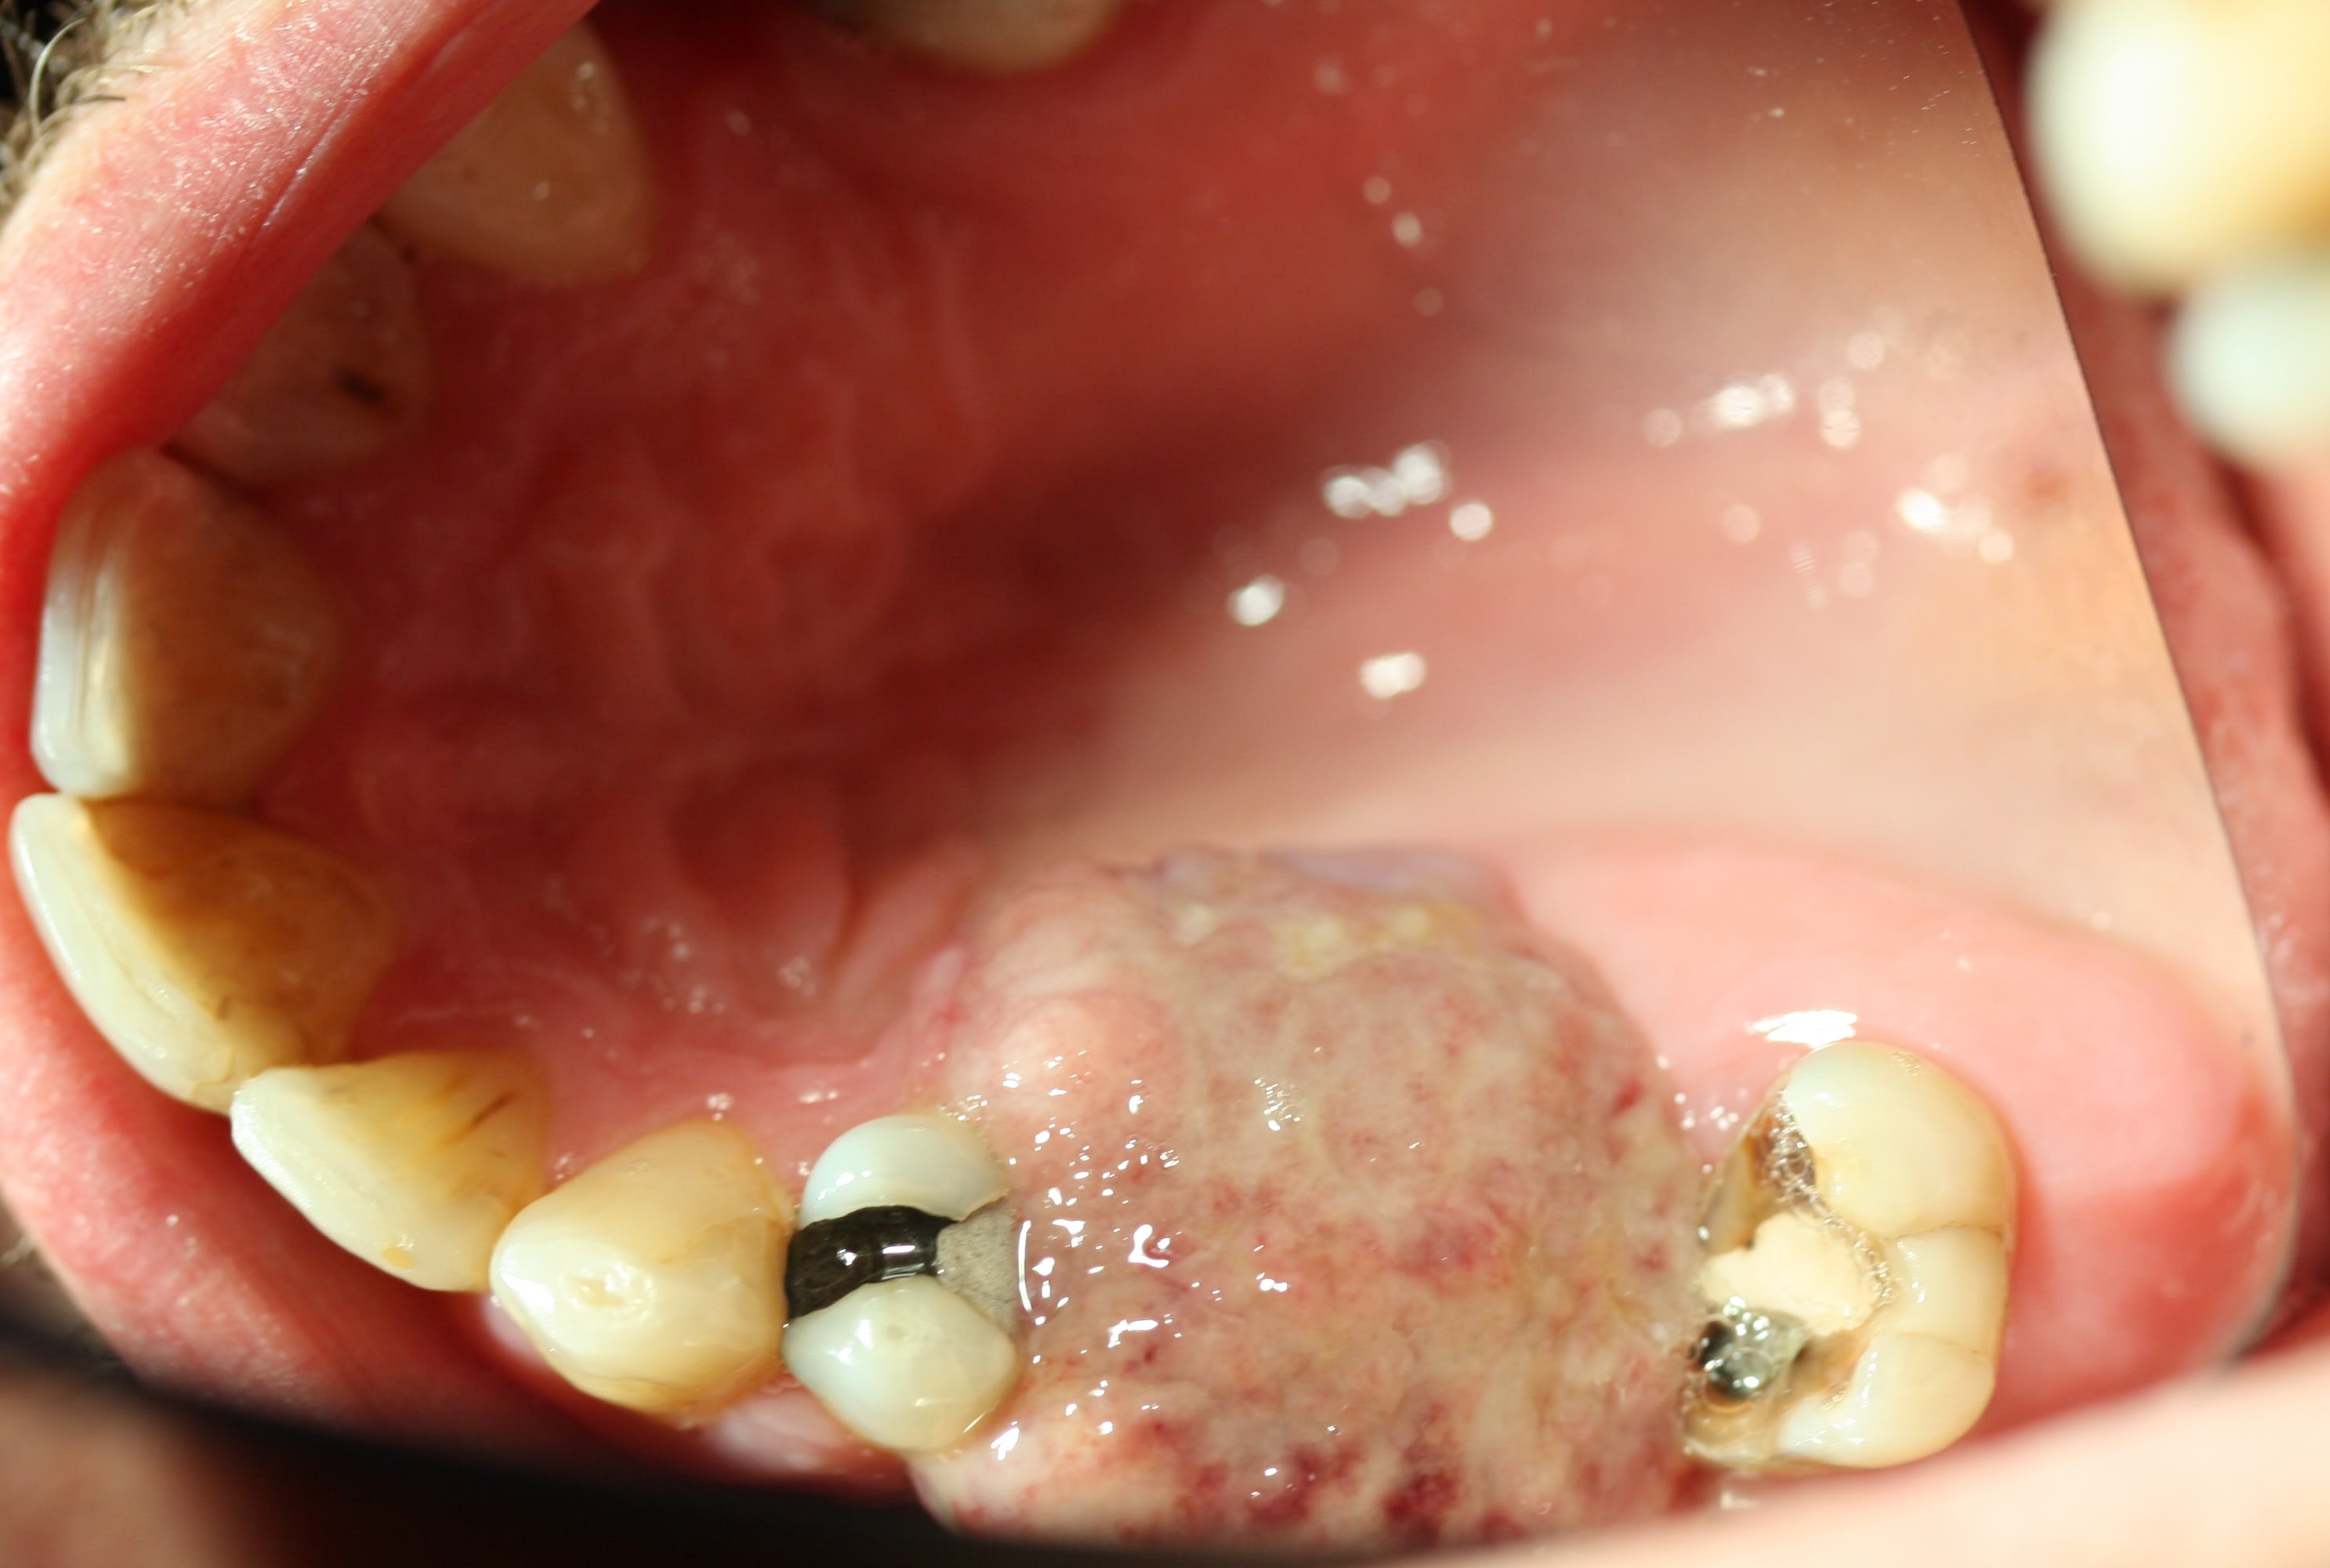

En continuant avec les envahissements de sinus.

Une idee de diagnostic? Evolution depuis 3 mois, facilement mobilisable, saignement a palpation, qui a envahit le sinus.

Patient a aucune douleur. Pas d adenopathies peripheriques.

En bonus un autre probleme de sinus...

C est un Granulome central a cellules geantes a progression lente. ( Image clinique tres proche carcinome epidermoide)

Traitement envisage est injection de biphosphonates( Denosumab) pour reduire la lesion. Cela permettrait d eviter une resection en bloc type hemimaxillectomie et reconstruction par fibula.